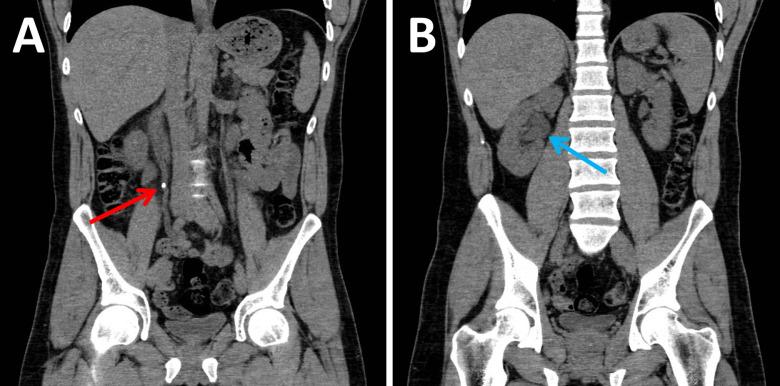

教学案例:尿路结石

Educational Case: Urinary Stones.